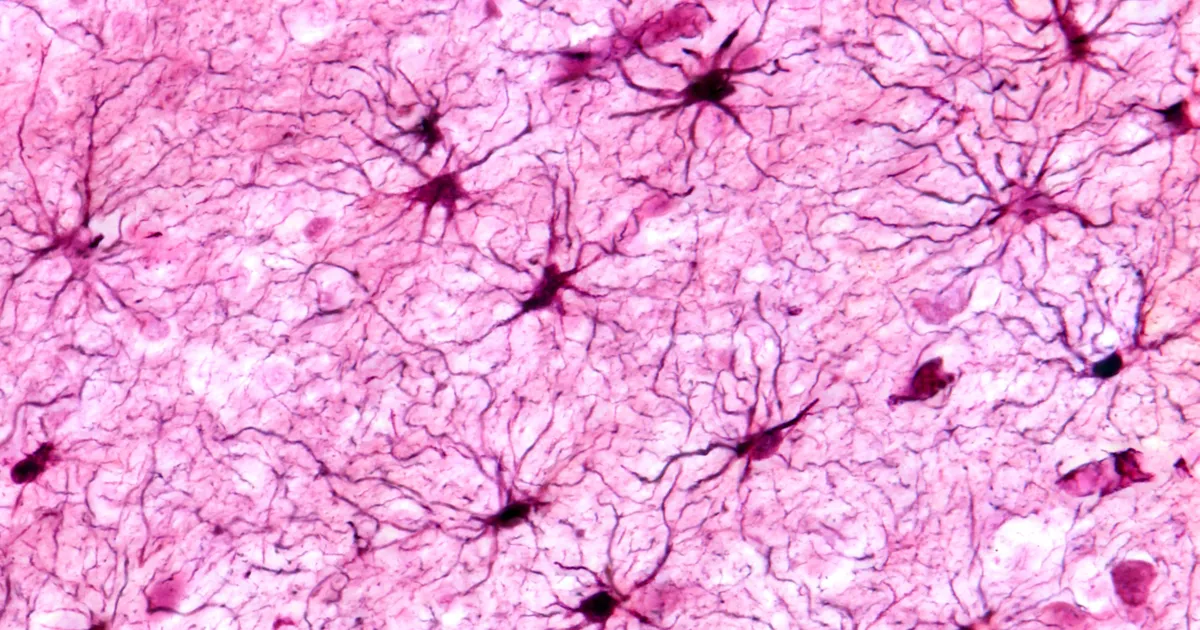

AVASTUS ⟩ Ajus elutsevad «tähekesed» säilitavad mälestusi

Baylori meditsiinikolledži teadlased uurisid tähekujulisi ajurakke, mida nimetatakse astrotsüütideks, mis toimivad mälestuste mikro-hoidlatena. Neid rakke haldavad spetsiaalsed ...